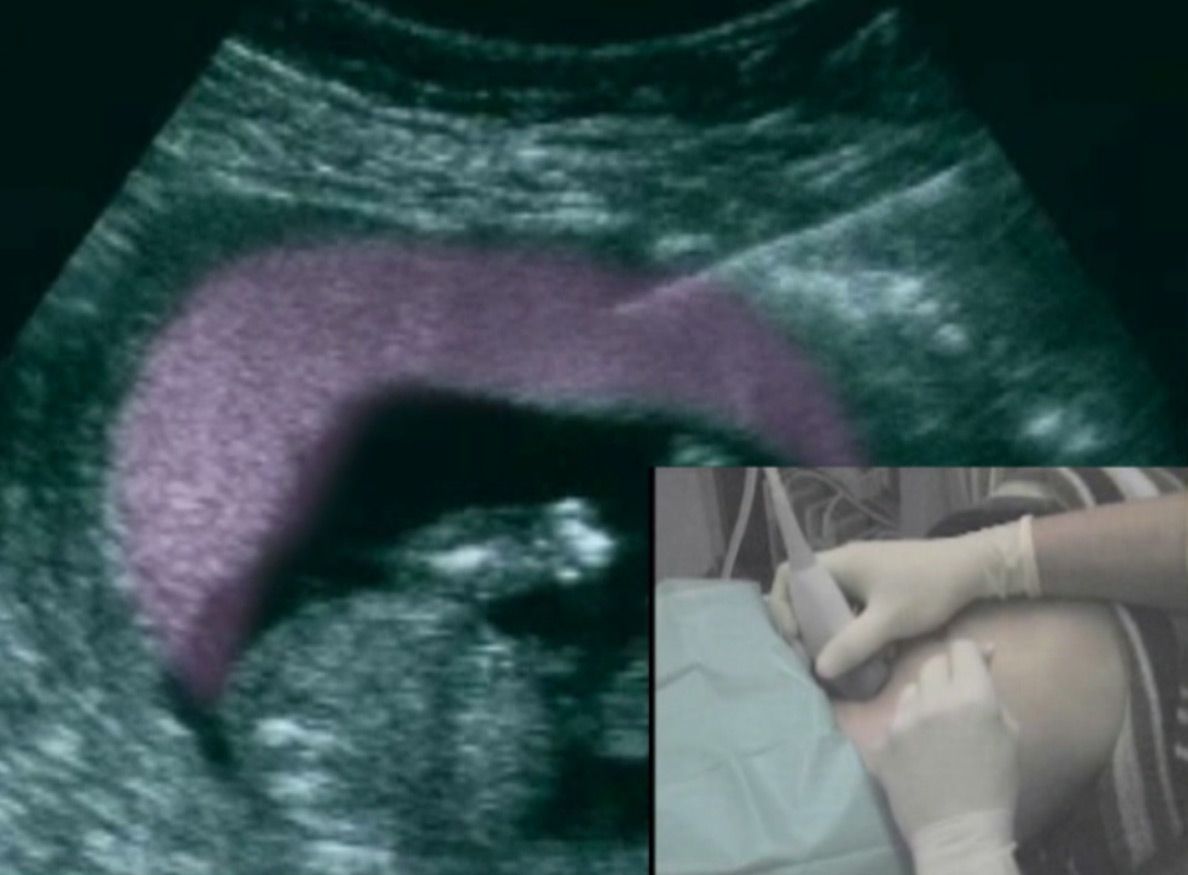

Die Punktion erfolgt im Untersuchungszimmer. Zunächst die Bauchhaut desinfiziert und ein steriles Tuch über die Beine gelegt. Sie erhalten zunächst eine lokale Betäubung unter die Haut. Mit der eigentlichen Punktionsnadel wird dann eine Gewebeprobe aus dem Mutterkuchen gewonnen. Der Untersucher verfolgt den Verlauf der Nadel mittels Ultraschall und kann auf diese Weise die korrekte Position der Nadel bestätigen. Die Fruchthöhle wird nicht berührt. Nach korrekter Platzierung der Nadel im Mutterkuchen, wird eine Spritze mit einer Nährlösung aufgesetzt  und diese unter Sog zurückgezogen.

Die gesamte Punktion dauert etwa 1-2 Minuten und wird von den meisten Patientinnen als nicht schmerzhaft beschrieben. Insgesamt werden etwa 15g Chorionzotten gewonnen, die sich im Nährmedium befinden. Diese werden an Humangenetik zur weiteren Diagnostik weitergeleitet. Abschließend erfolgt nochmals eine Ultraschallkontrolle.